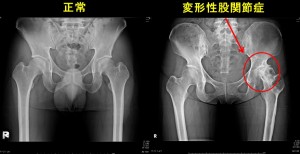

下の画像をご覧ください。

この画像は、整形外科でレントゲン撮影を行い変形性関節症と判断されたものです。

○の部分にご注目ください。

関節軟骨は減り、骨も変形し始めているのが確認できます。

しかし、この時点でお客さんの膝に痛みはありません。

「変形性関節症」 確かにそうです。

画像を見る限り、誰もがそのように判断するのは間違いないでしょう。

だからと言って、骨の変形=痛み、軟骨のすり減り=痛み ではないのです。